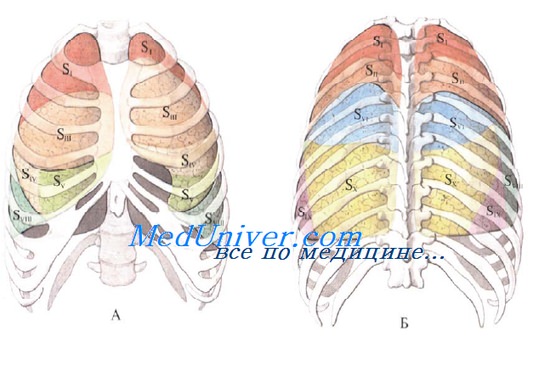

Анатомические изображения сегментов легких различных животных

Раздел: Другие животные